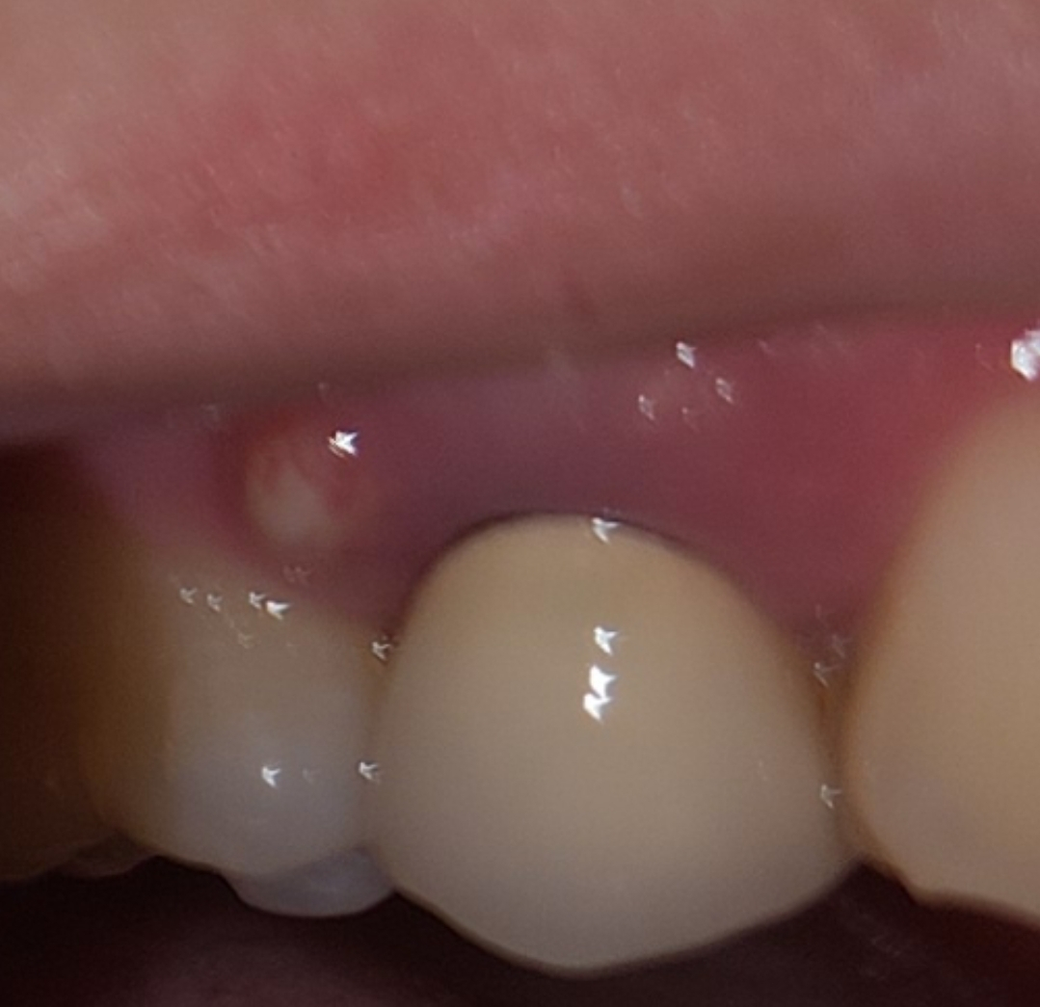

가끔씩 잇몸에 물집 같은것이 갑자기 생기고 엄청 아파집니다.

어금니쪽인데 일년에 한두번씩 저렇게 갑자기 생기고 너무 아파집니다. 원인이 무엇이 있을까요?...

예전에 충치치료를 위해 신경치료했던 위치이고 그 이후로부터 가끔씩 생겼다가 약먹고 낫고 생겼다가 약먹고 낫고를 반복했는데.. 이번은 특히나 더 아픈 느낌이네요 ㅠㅠㅠㅠ

고름이 차 있는 잇몸농양입니다. 가능한 빨리 치과 내원하여 고름 터트리고 항생제 복용해야 합니다.

사진에 보위는 검은색 부위는 충치가 아니고 보철물의 금속이 비춰보이는겁니다. 저 물집이 단순이 잇몸염증이면 잇몸치료를 받으시면되지만, 치아 뿌리끝에서 나오는 염증이라면 신겨치료를 받으셔야될수도 있습니다.

현재 사진으로 보았을 때는 과거에 치료한 치아에 문제가 발생한 것으로 보입니다. 치료한 치아에 농이 차올라서 바깥으로 나오고 있는 것이며 이를 만성 농양인 sinus tract일 가능성이 매우 높습니다. 현재 잇몸 상태를 보았을 때도 해당 치아에 염증이 심해보이며 치과 방문 후 해당 치아에 대한 평가를 받아보셔야할 것 같습니다. 아마 해당 치아에 치조골도 많이 손상되었을 가능성이 큽니다.

잇몸에 사진과 같은 고름이 나오는 경우에는 어떤 원인으로 인해서 치주질환에 문제가 생겼을 경우입니다.

주로 치근의 파절이나 신경관감염에 의해서 생기는경우가 많습니다.

치근의 파절이라면 발치를 해야 할수 있으며 신경관의 감염때문이라면 신경치료가 필요할수 있습니다.

내부의 금속 때문에 전체적으로 빛깔이 탁하며, 금속 일부가 노출되어 잇몸 경계선이 시커멓게 보일 수 있습니다.